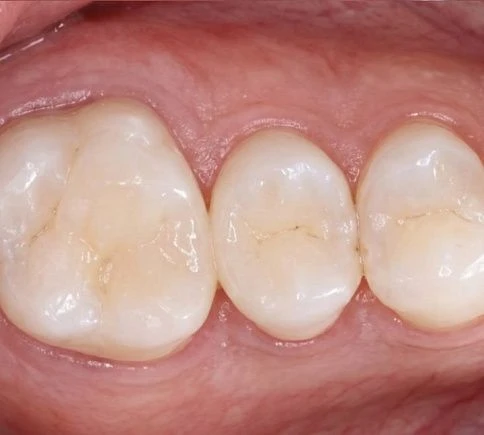

Коронки Е-max — это новый подход к протезированию зубов. Керамические безметалловые коронки имеют повышенную прочность и прекрасные эстетические свойства, поэтому их рекомендуют для реставрации передних зубов (зоны улыбки). Для изготовления коронок на зуб Е-max используются специальные блоки-заготовки, из которых по индивидуальным параметрам вытачивают микропротез. Стоматологи-ортопеды клиники «Доктор Смайл» создают модели протезов на компьютере, что повышает точность результата.

Безметалловые коронки Е-max изготавливаются из качественной стеклокерамики (дисиликата лития). Этот высокопрочный материал не вызывает раздражения и аллергии, и отличается длительным сроком службы. Такие протезы выглядят натурально, повторяя полупрозрачность и оттенок естественной эмали.

Технология обеспечивает полупрозрачность и оттенок натуральной эмали, поэтому используется для реставрации единичных моляров, резцов и премоляров, участвующих в улыбке.

Кроме того, коронки E-max CAD показывают более высокую степень прилегания в области шейки зуба. При правильной установке под протез не попадают бактерии, что увеличивает срок службы и сводит к минимуму вероятность осложнений.

Будет ли заметна разница между Е-max и натуральными зубами при улыбке?

Наши специалисты внимательно подходят к подготовке и подбирают оттенок коронки, идеально повторяющий натуральную эмаль пациента. При правильном изготовлении и установке отличить искусственную коронку от натурального зуба невозможно, и удается полностью восстановить эстетику улыбки.